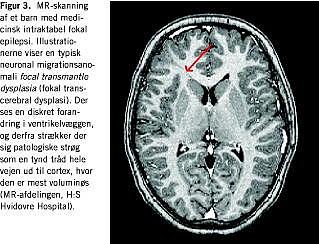

Formålet med disse er, ud over at vurdere epilepsiens betydning, at diagnosticere anfaldenes udgangspunkt, bedømme sandsynligheden for anfaldsfrihed og risikoen for komplikationsfølger. Det er afgørende at påvise, om et bestemt hjerneområde, der er ansvarligt for anfaldene, præcist kan udpeges. Ingen enkeltstående undersøgelse kan afklare dette. En af de væsentligste undersøgelser er en videooptagelse af flere anfald samtidig med EEG-registrering. Beskrivelse af anfaldets klinik (semiologi) er også en væsentlig faktor ved hypotesedannelsen om anfaldets udgangspunkt. Derudover spiller MR-undersøgelsen en afgørende rolle. Almindelig standard-MR-skanning er oftest ikke tilstrækkelig. Påvisningen af f.eks. diskrete kortikale dysplasiforandringer er tidskrævende og kræver stor radiologisk erfaring, meget tynde snit, tredimensional teknik og høje Teslaværdier med større opløselighed af MR-billederne (Figur 3 ). EEG-undersøgelsen kan især hos mindre børn være vildledende på grund af den umodne hjernes høje eksitabilitet. Derfor vil et supplement med funktionelle billeddannende teknikker nogle gange være nødvendigt. En SPECT-undersøgelse med indgivelse af radioaktivt sporstof under et anfald viser oftest hyperaktivitet af blodgennemstrømningen i den epileptogene zone. Tekniske vanskeligheder gør, at denne resursekrævende undersøgelse sjældent kan gennemføres. PET er især værdifuld, når MR-skanningen viser negativt resultat. Et område med lav metabolisk aktivitet er et stærkt indicium for den epileptogene zone (Figur 4 ). En neuropsykologisk test er vigtig for at forudse mulige deficit ved den planlagte operation og skal altid gennemføres før operationen og 1-2 år senere for at vurdere effekten af indgrebet. Endelig bliver alle børnene undersøgt af en børnepsykiater for mulige adfærdsforstyrrelser og af en øjenlæge med henblik på synsfeltsudfald.